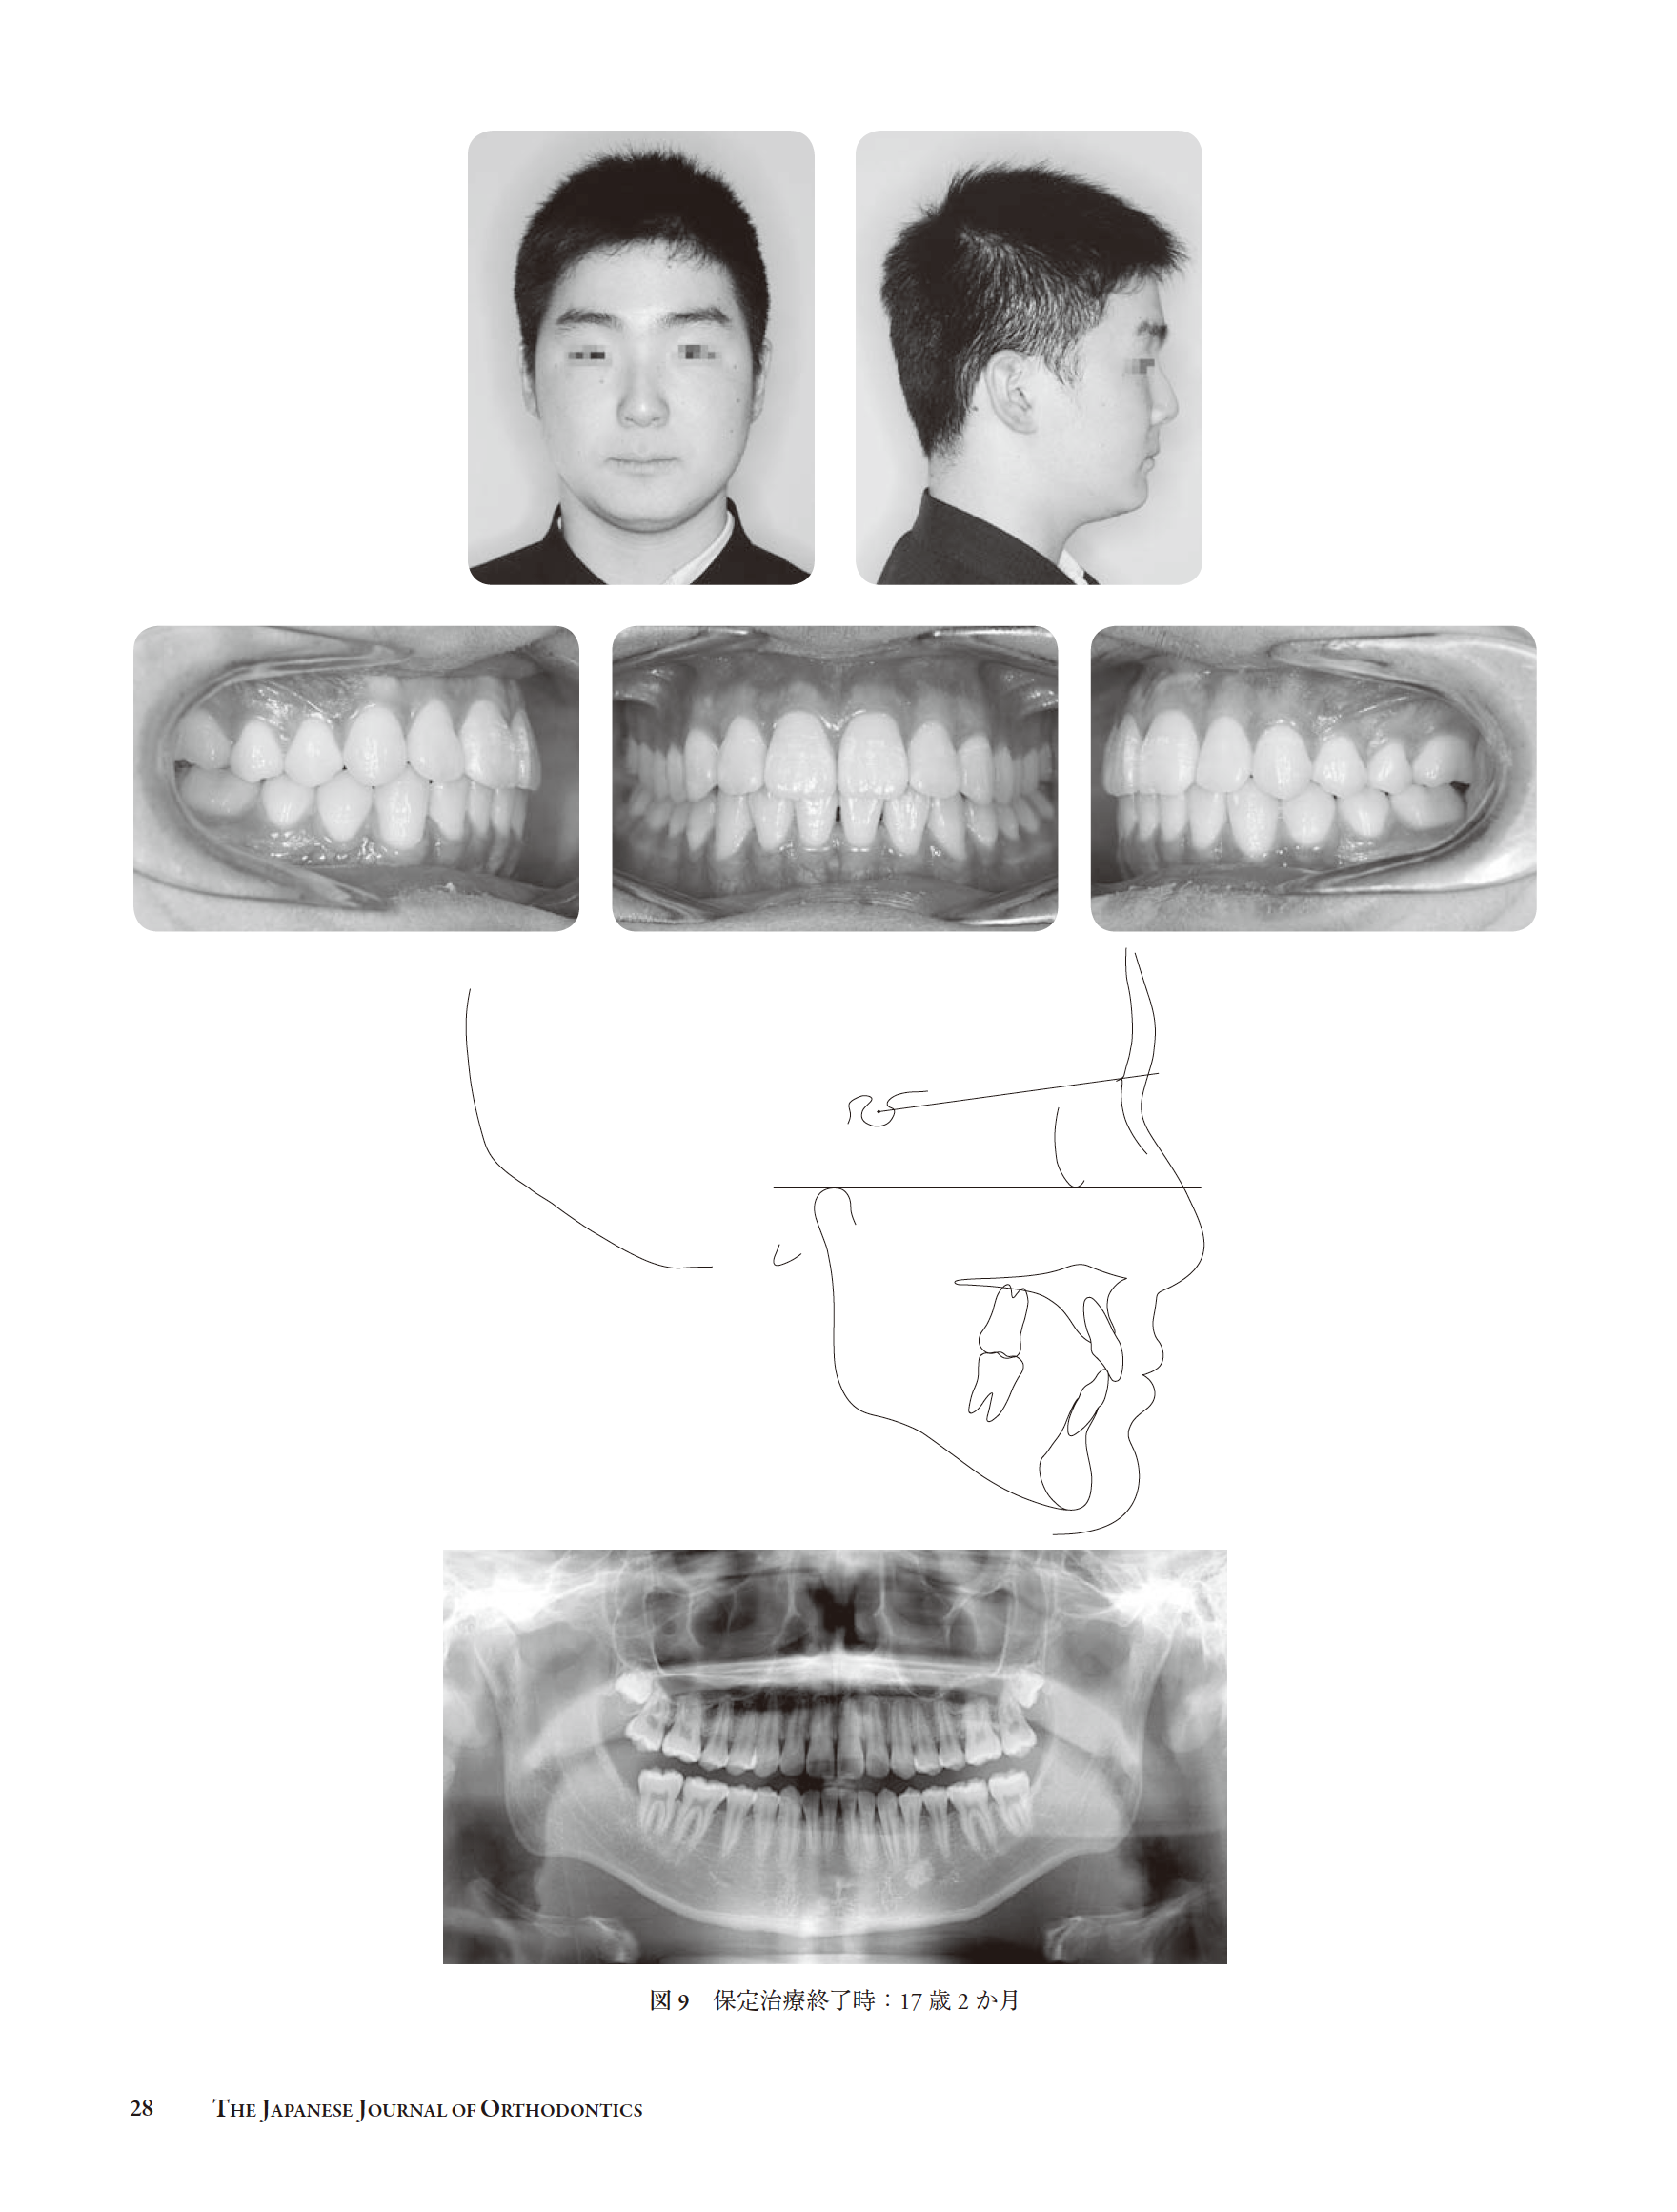

早期治療を行なった上突咬合の一治験例(和島)